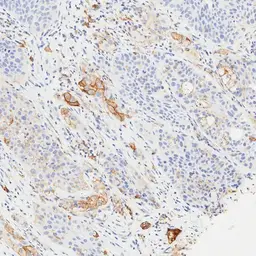

Optimal staining result of human NSCLC, tissue core no. 5, using PD-L1 antibody [H302] HistoMAX™ on Leica Bond III, following the vendor recommended protocol settings.

Distinct membranous reactivity (weak-to-moderate intensity) is observed in approximately 40% of tumor cells. Accordingly, the specimen is categorized as TPS Low (≥1–49%).